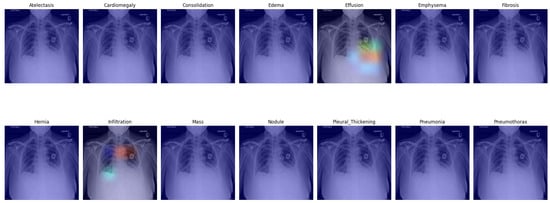

3.5. Visual Representation

In this section, we present a visual interpretation of the learned features, using the Gradient-weighted Class Activation Mapping technique (Grad-CAM) [33]. Grad-CAM offers a technique to produce “visual explanations” for decisions from a broad array of CNN-based models, enhancing their transparency and interpretability. Grad-CAM utilizes the gradients of any target concept (e.g., ‘Effusion’ in the current context) flowing into the final convolutional layer to generate a coarse localization map. This map highlights the crucial regions in the image for predicting the concept [33]. Unlike prior methods, Grad-CAM can be applied to various CNN architectures without the need for re-training or architectural modifications.

In Figure 5, we present a visual representation of our proposed enhanced model wherein the pleural effusion is marked in the fifth image in the first row, confirmed by a radiologist. In the second image in the second row, however, infiltration is falsely suggested, and the aortic knob was marked instead (red). Infiltration is less likely but probable in the right lower lung area. Infiltration is also likely as an underlying factor for the effusion on the left side; this was not suggested by the algorithm. Cardiomegaly was also not suggested, although it can be visually confirmed.

Figure 5. Grad-CAM of our proposed model with enhanced classifier.